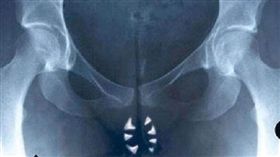

「陰牙人」真的存在?醫師:不無可能

黑色幽默電影《陰牙人》(Teeth)於2007年上映...